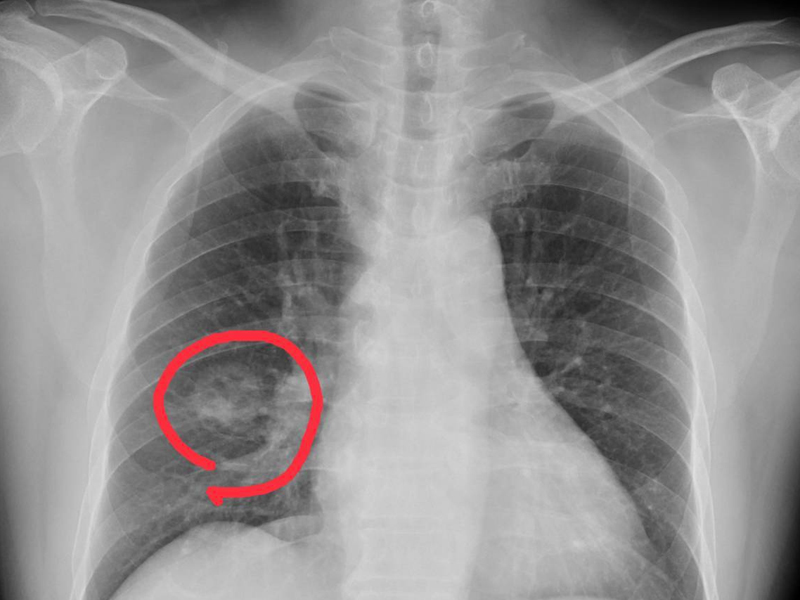

手腳出現 4 種異常,可能是得肺癌了,千萬不要大意